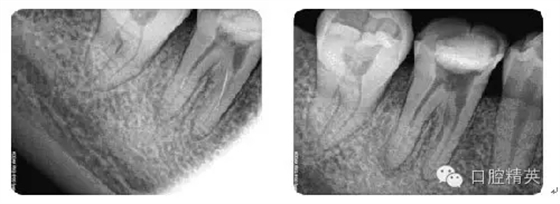

病例1:常規(guī)根管治療

病例2:各型MB2根管